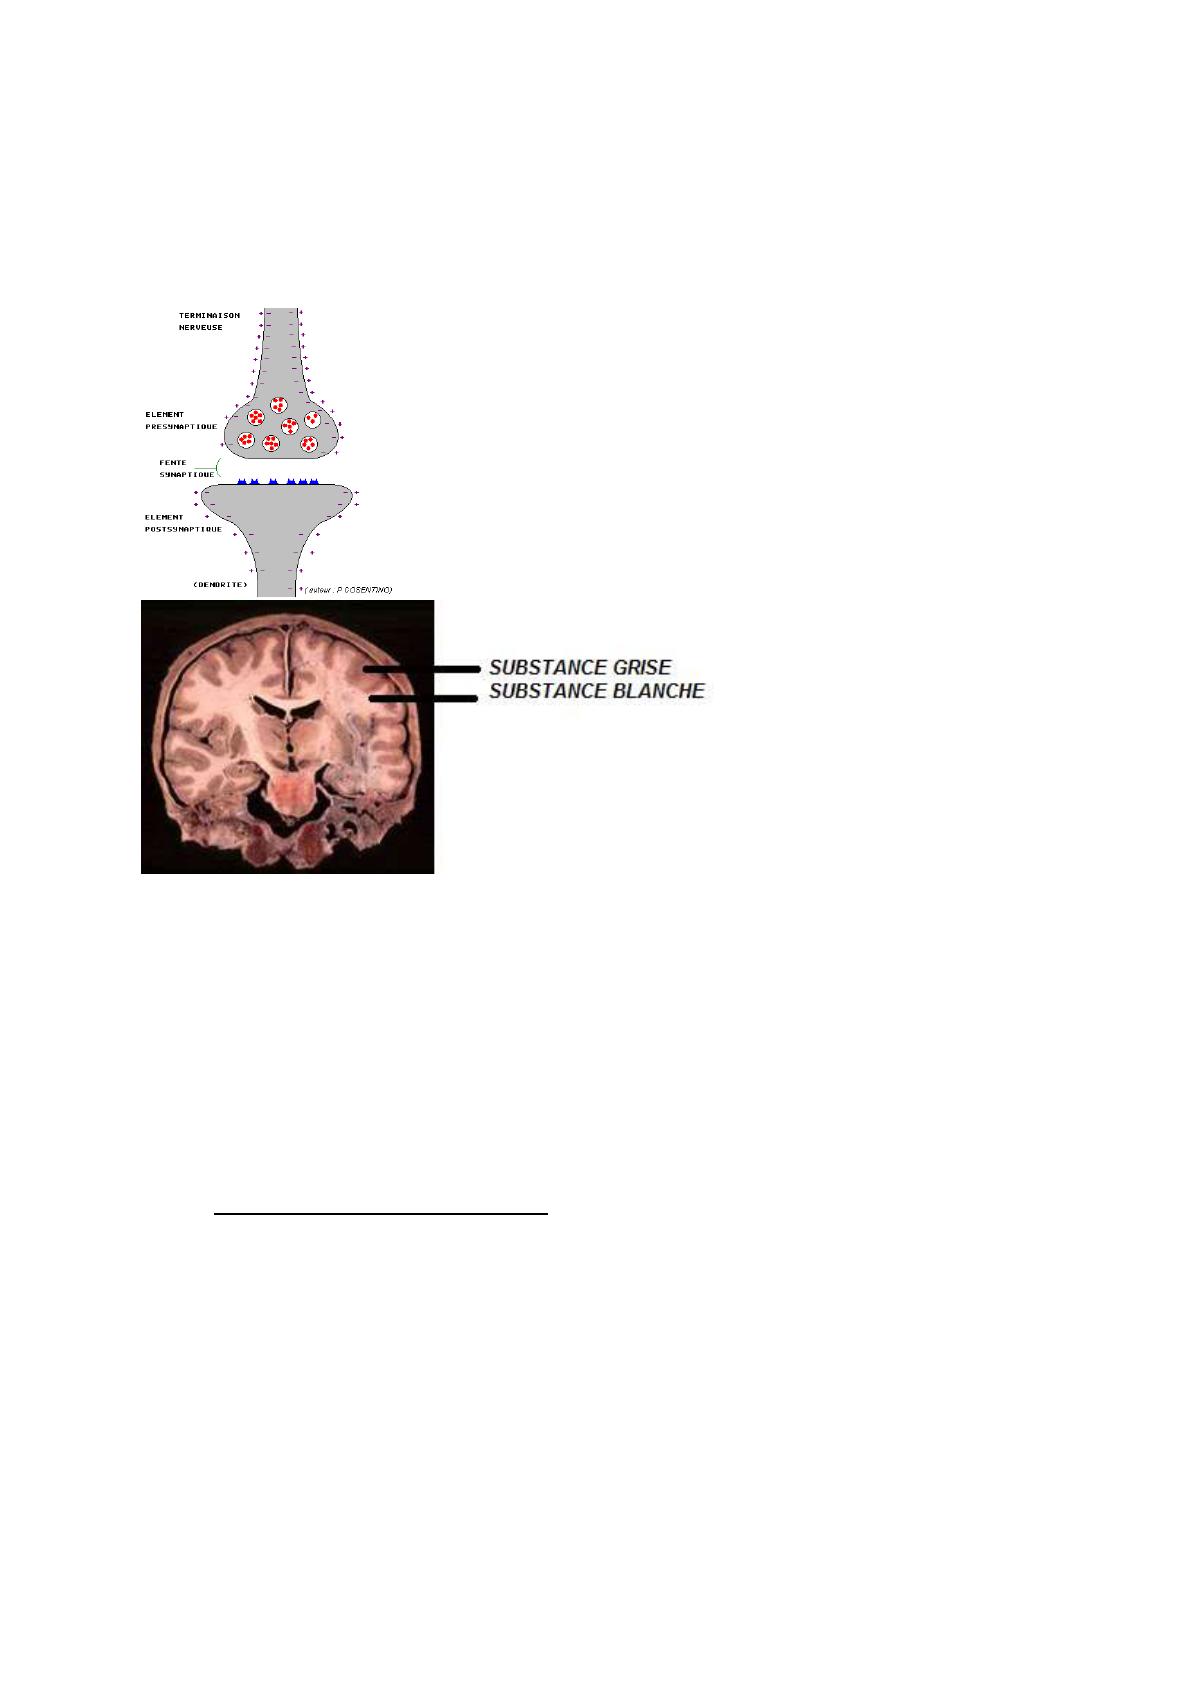

Le corpuscule nerveux terminal est séparé des neurones voisin par un mince espace

= fente synaptique, cette jonction fonctionnelle est appelée synapse.

NB: Les neurones sont rapproches les uns des autres, mais ils ne se touchent

jamais.

Structure : Substance blanche : groupements denses d’axones myélinisés

Substance grise : contient surtout des corps cellulaires et des neurofibres myélinisés